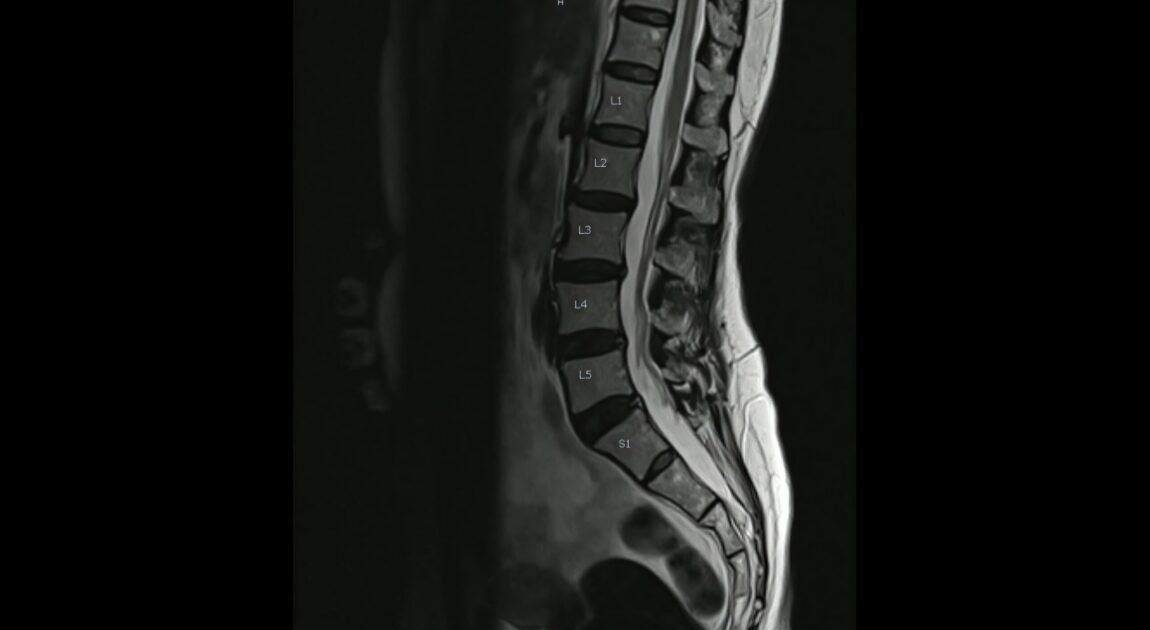

現代の整形外科外来において、私たちはある種のパラドックスに直面しています。診察室のモニターに映し出されたX線写真には、見るも無残に潰れた関節裂隙と、鋭く突き出した骨棘が記録されているにもかかわらず、当の本人は「たまに違和感がある程度です」と涼しい顔で笑っている。その一方で、画像上は年齢相応の極めて軽微な変化しか見られない患者が、夜も眠れないほどの激痛を訴え、杖なしでは歩行もままならないという状況も珍しくありません。かつて私たちは、関節の痛みを「機械的な摩耗」の結果として捉えてきました。長年の使用によってタイヤの溝が減るように、軟骨がすり減り、骨同士がぶつかるから痛むのだ、と。しかし、最新の痛みに関する科学、すなわちペインサイエンスの世界では、この「構造=痛み」という単純な線形モデルはすでに過去のものとなりつつあります。

臨床的な研究において、画像上の変形の程度と自覚症状の強さの相関が驚くほど低いことは、多くの大規模調査で裏付けられています。例えば、変形性膝関節症(KOA)を対象とした研究では、画像診断で中等度以上の変形が認められる人のうち、実際に慢性的な痛みを抱えているのは半数以下に過ぎないという報告もあります。これは、私たちが「病変」と呼んでいるものの多くが、実は加齢に伴う自然な組織の変化、いわば「白髪」や「顔のしわ」のようなものに過ぎない可能性を示唆しています。では、構造的な変化が主犯ではないのだとしたら、一体何が痛みの「ボリューム」を決定しているのでしょうか。その答えは、関節という局所的な組織から、それを取り巻く神経免疫学的なネットワーク、さらには脳という巨大な情報処理系の中に隠されています。